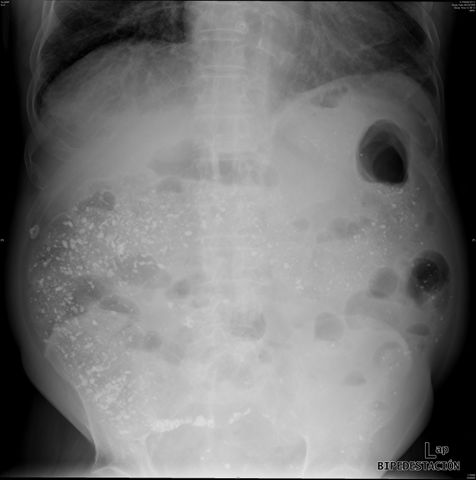

Diverticulosis de colon.

Diverticulosis de colon. Megacolon.